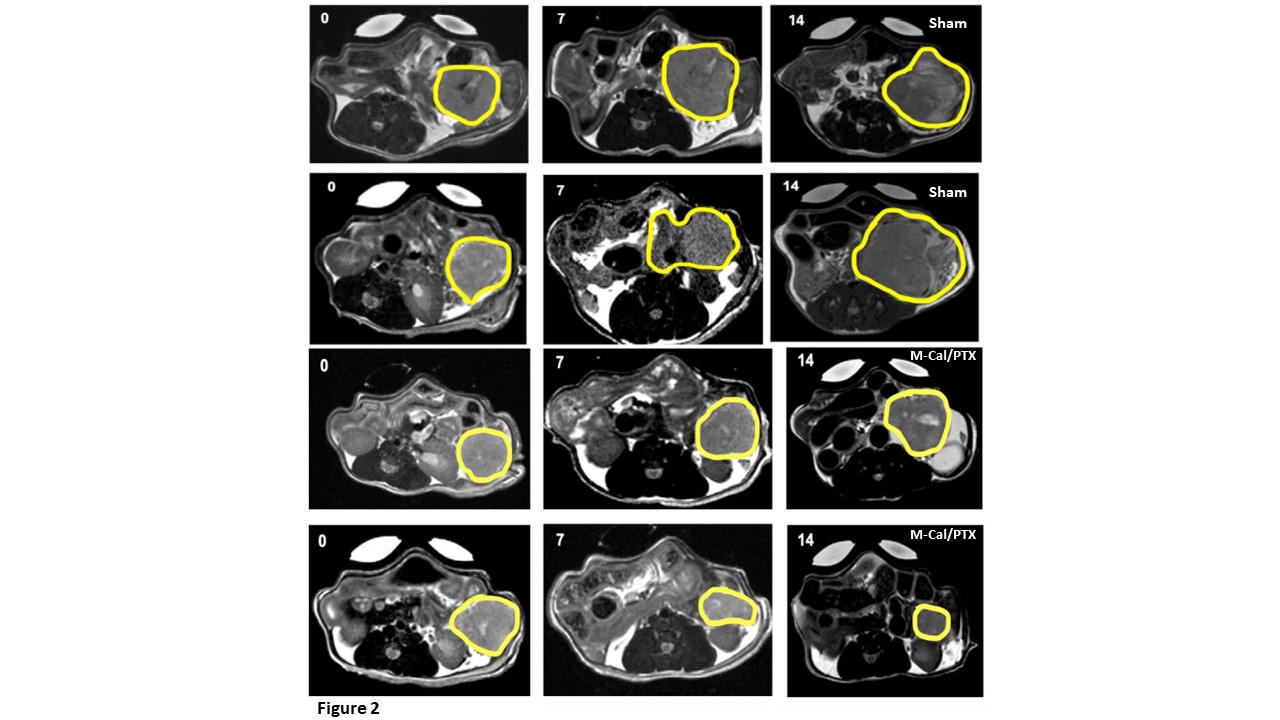

Purpose: PDAC is an aggressive malignant neoplasm which continues to carry very poor prognosis despite advances in therapies over the past decade. The PDAC stroma-tumor microenvironment contributes to resistance mechanisms for optimum drug delivery and antitumor activity. Calcipotriol (Cal) is a stroma modulator, that is hypothesized to enable better drug delivery of paclitaxel (PTX) into the tumor tissues and enhance its cancer cell cytolytic activity. We recently developed and validated a UPLC-MS/MS assay for simultaneous quantifications of Cal and PTX at LLOQ of 0.5 ng/ml and developed a nano-polymeric micelle drug delivery system, loaded with Cal and PTX (M-Cal/PTX), for treatment of PDAC. Biodistribution studies using the micellar system confirmed Cal/PTX accumulation in orthotopic mouse PDAC models. The pharmacodynamics (efficacy) and safety assessments of M-Cal/PTX in the mouse PDAC model are presented herein. Methods: To perform short-term efficacy, and safety studies, we used orthotopic Kras* mouse model of PDAC. The primary endpoints were to assess: 1) tumor response as measured by T2-MRI; and 2) the change in circulating stroma markers with M-Cal/PTX treatment. Mice received IV doses of M-Cal/PTX (0.5 mg/kg Cal and 5 mg/kg PTX); the dosing scheme used is summarized in Figure 1. Mono formulation of Cal (M-Cal) (N=3), a mixture of mono-formulated Cal and mono-formulated PTX (M-Cal + M-PTX) (N=4), a combination of M-Cal and Abraxane (M-Cal + ABX) (N=3) and a cremophor formulation of Cal and PTX (Crem-Cal + PTX) (N=6) were included as controls. The tumor size was measured by means of T2-MRI and the corresponding volumetric quantifications were obtained. The effects of treatment on the circulating levels of TIMP1, TSP2 and MMP7 were evaluated by ELISA. A survival study was conducted to estimate the treatment benefit in terms of overall survival. Results: In the M-Cal/PTX group, there was a 75% response and one animal had significant tumor progression. In contrast, 75% of mice in the sham group showed tumor progression (Figure 2). Similarly, the M-Cal/PTX treatment benefit was demonstrated by assessing tumor volume (Figure3A). Two animals in the M-Cal/PTX group showed a moderate increase in their tumor volumes from day 7 while one had tumor shrinkage at days 7 and 14. None of the animals in the sham group has tumor shrinkage. The effects of M-Cal/PTX on circulating plasma markers of stroma activity were measured. For TIMP1 a delayed response was observed (Figure 3B). The mean TIMP1 levels continued to decrease after the 4th dose (day 7) while the levels remained very high in the sham group. The effect of M-Cal/PTX on circulating TSP2 levels was rapid (Figure 3C). Reduction of TSP2 to baseline levels was achieved after the second dose and the levels remained low through the 10th dose. M-Cal/PTX did not impact the circulating levels of MMP7 after 10 doses. Treatment with M-Cal/PTX caused significant decrease on alpha-smooth muscle actin (𝛼-SMA), another reliable marker for stromal activity, compared with the sham group. We looked at the Ki-67 (a proliferation marker) and matrix protein collagen, and both were significantly inhibited in the treatment group compared to the sham group. For survival analysis, animals that were administered M-Cal/PTX lived the longest (median of 54 days) compared to of 24 days for those received sham (Figure 3D). We finally examined the effects of treatment on body weight and other markers of organ health (albumin, liver enzymes, blood urea nitrogen, globulin, and total protein). No significant change in weight with M-Cal/PTX compared to the sham group, and no notable abnormalities in the laboratory markers in the treatment group. Conclusion: Our data shows that M-Cal/PTX is a potentially effective combination regimen for treatment of PDAC. Compared to sham and other treatment interventions, M-Cal/PTX was associated with reduction of stroma-related markers, better antitumor activity, and improvement in median survival of tumor-bearing mice. Furthermore, no changes in mouse weight in the M-Cal/PTX group or notable laboratory abnormalities suggesting a tolerable safety profile for this combination therapy at the tested dose. Additional preclinical studies are in progress to further explore and develop this optimal regimen for PDAC treatment.

Figure 2. T2-MRI measurements of PDAC tumors in sham and M-Cal/PTX groups. Tumors were measured at baseline (day 0), midpoint (day 7) and on day 14.